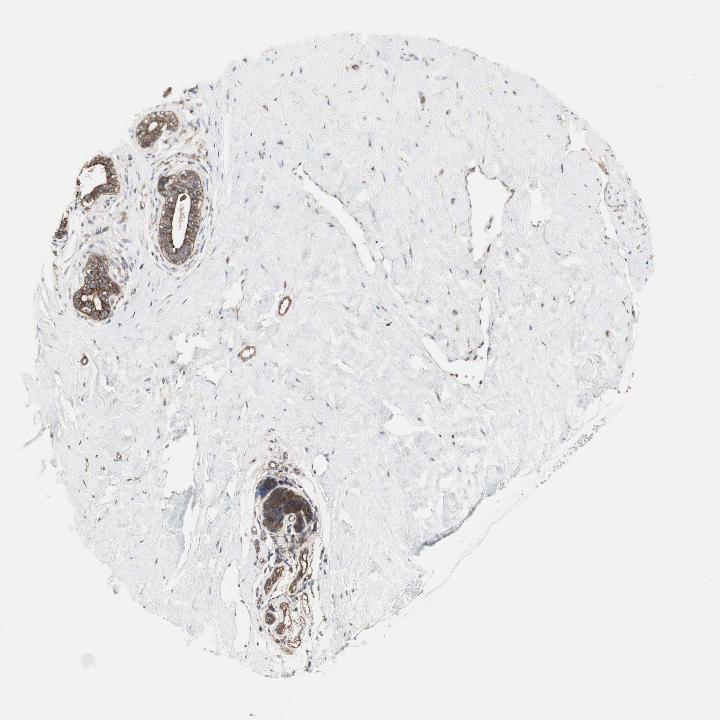

Antibody staining in the annotated cell types in the current human tissue is reported as not detected, low, medium, or high. This score is based on the staining intensity and fraction of stained cells.

Information about each individual sample is listed below, including gender, age, a tissue section image and estimated fractions of cell types. pTPM (transcripts per million) values give a quantification of the gene abundance which is comparable between different genes and samples.